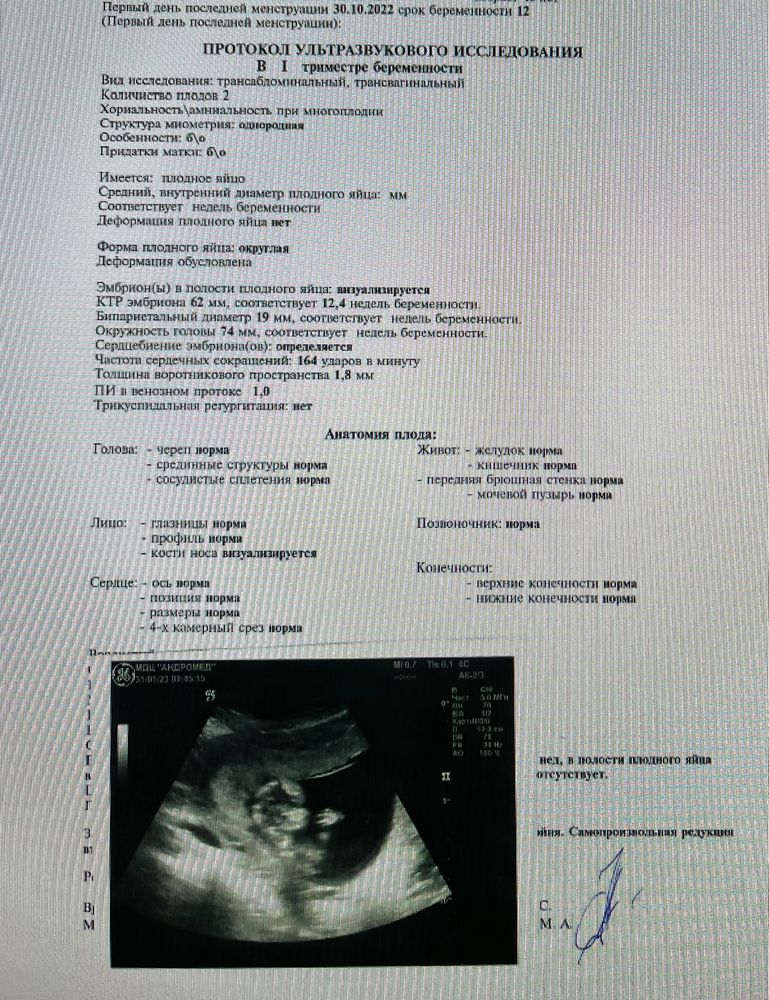

Первый скрининг подтвердил самопроизвольную редукцию одного эмбриона. Генетик сказала, что возможно с моей анемией это и к лучшему... Но нам было не легче от этих слов.. грустно и сейчас😥

По узи -всё хорошо с малышом. Я ждала анализ крови и мысленно готовилась к амниоцентезу (в предыдущую беременность делали по показаниям-носик у малышки был маленький и мой возраст)

Анализ пришёл хороший и генетик сказала , что не требуется доп. обследование-всё отлично))🙂